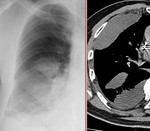

[画像診断]画像診断から見た胸水の考え方について(原因、性状) 2011-02-15